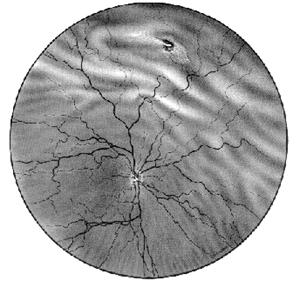

remanierile pigmentare apar mai ales la nivelul retinei periferice, sub forma de pete pigmentare stelate cu aspect osteoblastic, mai ales perivascular (Fig -17.7, vezi plansa).

Fig. 17.7 - Retinopatie pigmentara

examenul perimetric prezinta din stadiile incipiente aparitia unui scotom inelar (localizat intre 30 si 60 de grade in jurul punctului de fixatie), care evolueaza treptat catre periferie, cu ingustarea progresiva a campului vizual, ajungand ca in stadiile mai avansate sa devina tubular;

curba de adaptare la obscuritate este modificata in special in sectorul care corespunde bastonaselor (curba monofazica, inalta);

explorarile electrofiziologice (ERG, EOG) sunt intens alterate;

angiofluorografia nu este caracteristica; releva hiperfluorescenta difuza a periferiei retiniene.